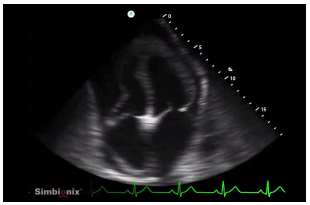

Foi realizada ultrassonografia cardíaca à beira-leito, em que foi obtida a seguinte imagem: